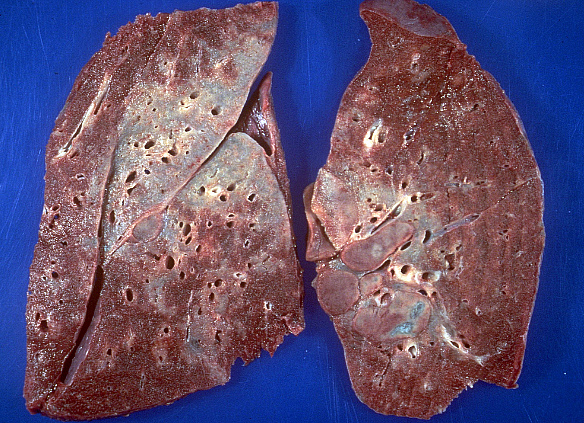

В 10% пациентов заболевание заканчивается склерозом легочной ткани и образованием «сотового» легкого. Такие состояния организма сопряжены с высоким риском летального исхода.

По статистике, у 40% больных диагноз выставляется по результатам изучения клинических симптомов и рентгенологического снимка легких. В остальных случаях окончательная диагностика требует проведения биопсии. При этом у пациента с подозрением на саркоидоз легких хирургическим путем изымается небольшая часть видоизмененной ткани. Гистологический и цитологический анализ биоптата определяет окончательный диагноз.

Пациенту необходимо помнить, что диагностическое исследование следует проходить у квалифицированного специалиста. Это связано с тем, что дифференциация гранулемного поражения проводится с диссеминированным туберкулезом и раком бронхоальвеолярной локализации.